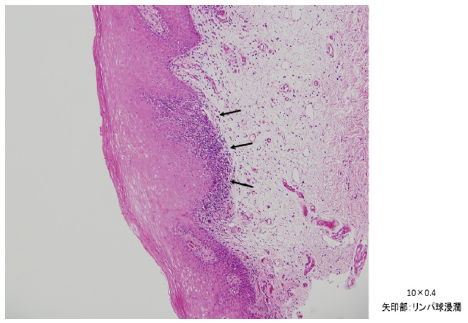

Histological findings by biopsy of right oral mucosa (Figure 2)

The specimen biopsied from the right buccal mucosal part is covered with a stratified squamous epithelium which partially elongated irregular epithelium leg with accompanying parakeratosis. Under the epithelium chronic inflammatory cells mainly lymphocytes are intermittently observed in focal (Figure 2a).

In the same area, liquid degeneration of the basal layer was also observed, possibilities of lichen planus were considered, but on this section the part showing characteristic findings was extremely localized, so it was diagnosed as leukoplakia (Figure 2b).